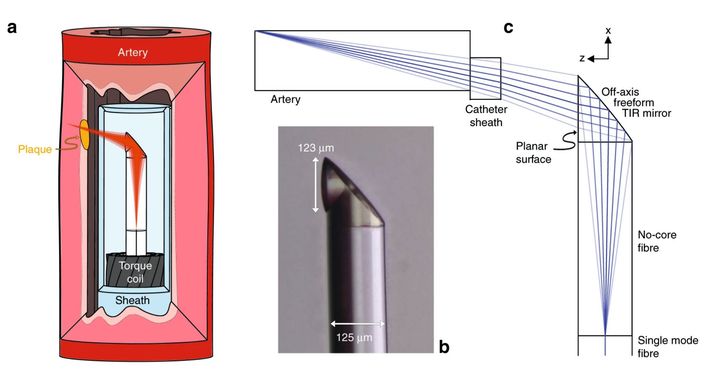

3D Printed Micro-Endoscope Developed

Researchers have developed a way to fabricate microscopic endoscopes using 3D printing technology.